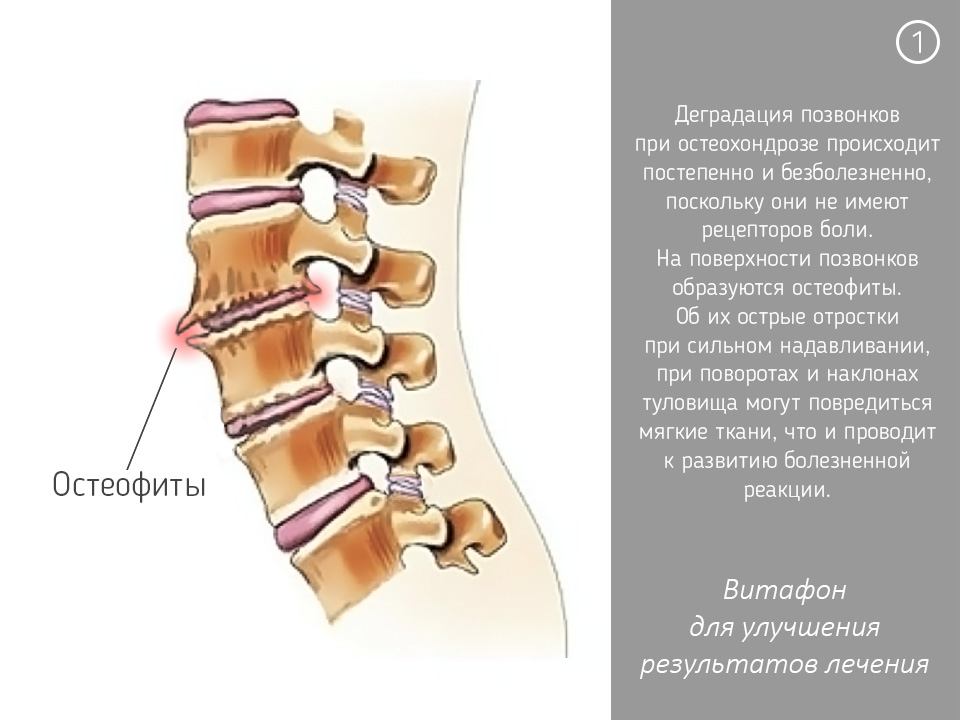

Позвонок Th10: анатомия и фото медицинских иллюстраций